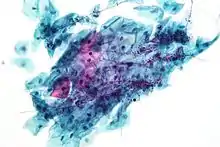

Micrograph of a normal pap smear

Micrograph of a Pap test showing a low-grade intraepithelial lesion (LSIL) and benign endocervical mucosa. Pap stain.